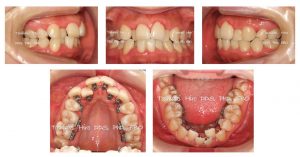

19歳女性、上下前歯の叢生を主訴に来院されました。

以前に他の医院で矯正治療を受けたとのことですが、上下前歯に著しい叢生が認められ、上下顎前歯臼歯ともに歯周病傾向が見られます。

Angle Class II subdivision(Rt: 4.0mm)

Skeletal II (ANB 5.7)

Crossbite of Rt molars

ALD: -5.0/-5.0 mm

14,24,35,45 missing

OJ/OB: 5.0/2.0 mm

Midline: A/ 2mm shift Lt, /A 2mm shift Rt

Periodontal problem

凸凹が著しいのですが、小臼歯は上下左右各1本がすでに抜歯されていますので、これ以上抜歯する事は出来ないことを御説明し、治療によって前歯が出ないよう臼歯を後ろに下げる治療計画を立て、治療後の側貌予測図をお見せして、御納得頂いた上で、上記診断の診断のもと非抜歯で治療を開始しました。

患者さんの希望により、上下とも外側からは見えない裏側に装置を付けました。